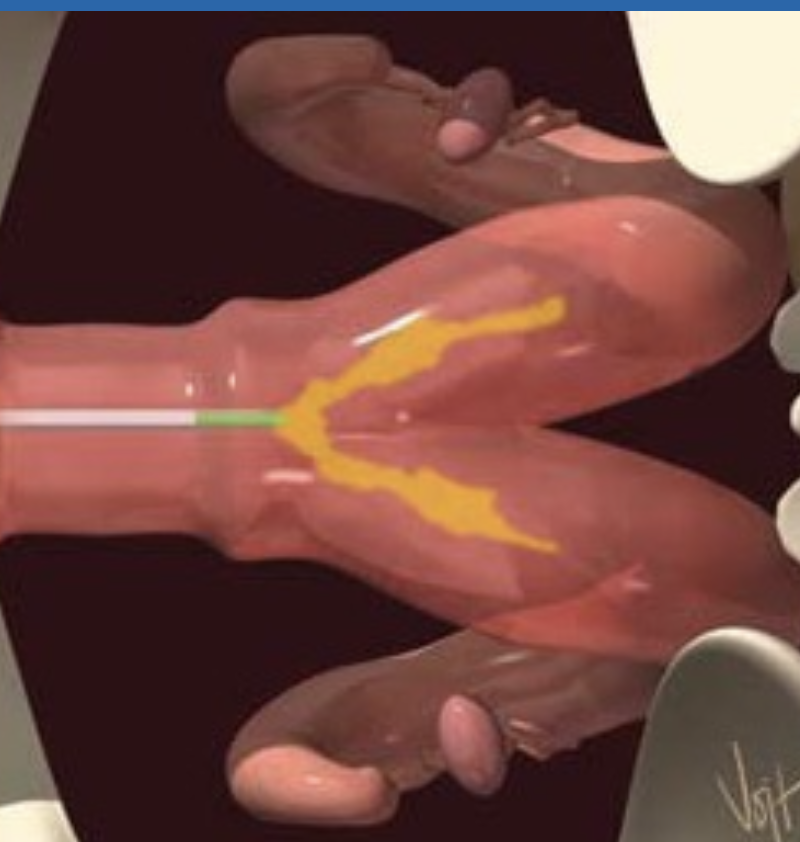

where is the correct placement of semen in the bovine female reproductive tract?

body of the uterus (between the internal os of the cervix and the bifurcation)